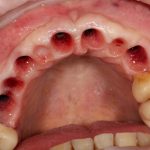

Например, в таком случае:

я бы зассал делать остеотомию предпочёл бы другой метод остеопластики